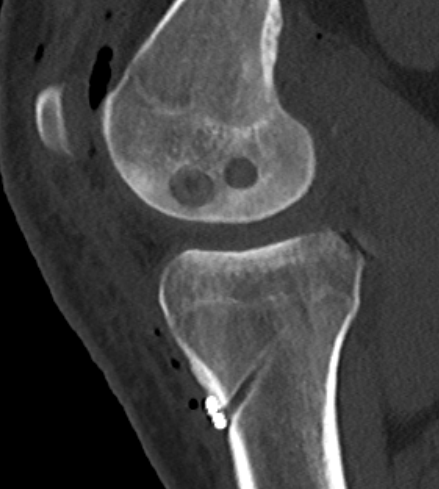

Acute femoral peel off of PCL

Acute Surgical Options

1. Repair bony avulsion

2. Acute suture repair of femoral peel off +/- augmentation

Acute repair of femoral peel off with suture tape augmentation

Indication

Femoral avulsion of the PCL

Acute injury

Technique

Repair to PCL to femoral insertion with sutures

Pass suture tape through tibial insertion to femoral insertion PCL to augment